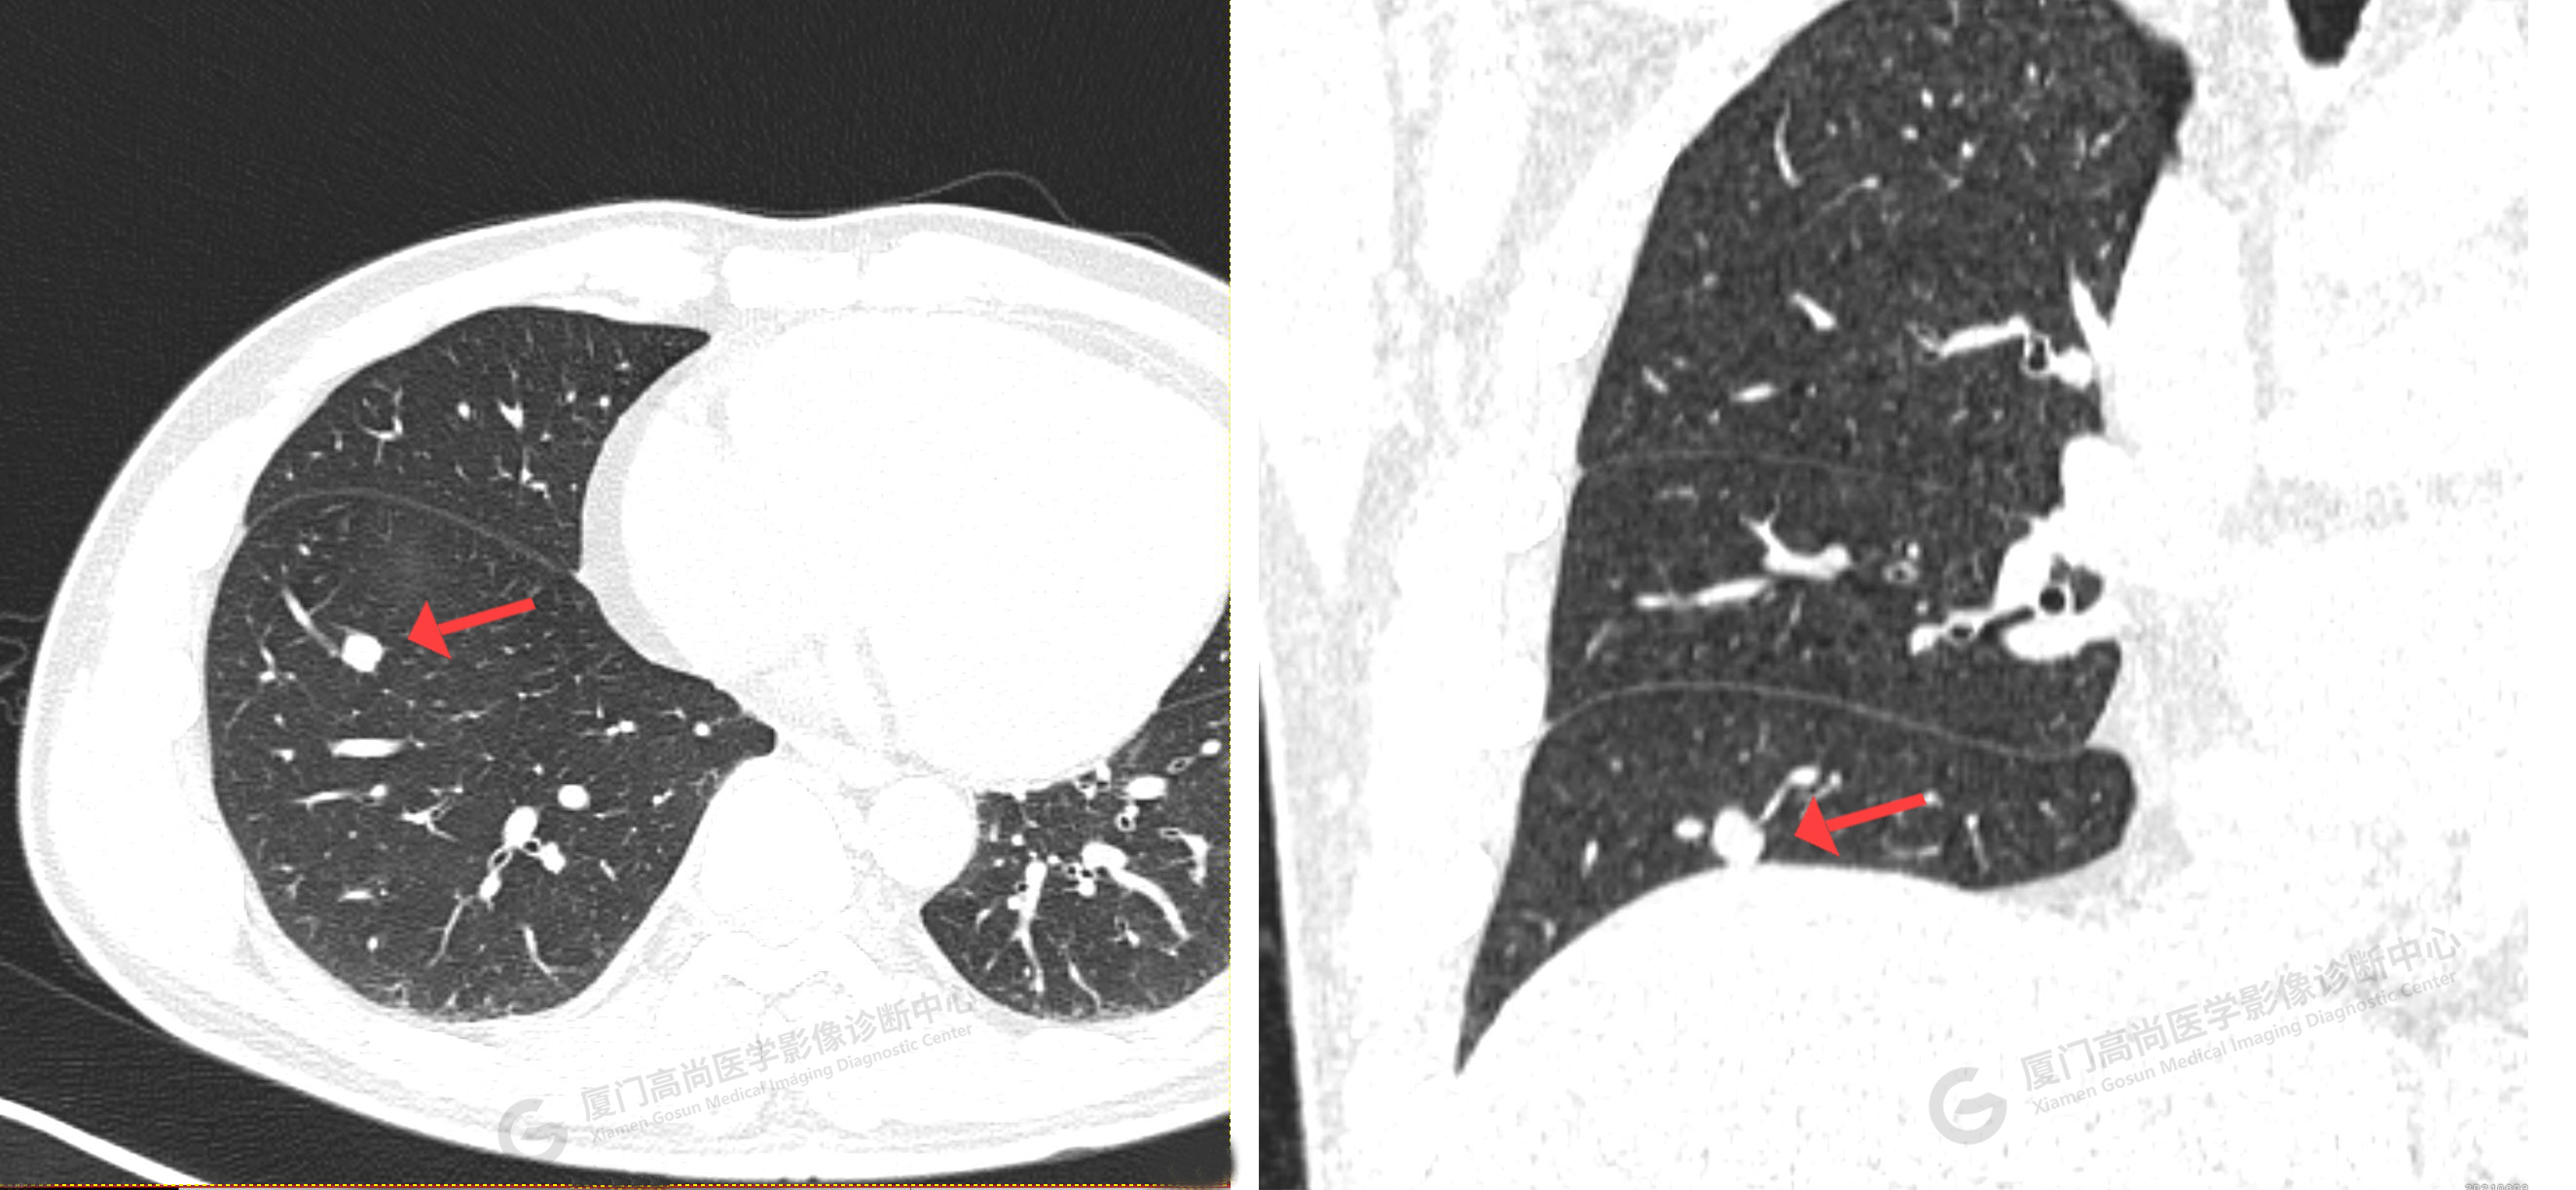

CT影像圖

靶掃描影像圖

靶掃描示:右肺下葉實(shí)性結(jié)節(jié),考慮腫瘤性病變可能性大,建議PET-CT進(jìn)一步檢查。2、左肺上葉尖后段磨玻璃結(jié)節(jié)及右肺上葉淡薄小片絮影,建議短期隨診復(fù)查。